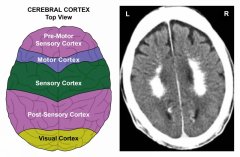

Úroveň mozku a orgánů: Konflikty odloučení odpovídají pokožce (epidermis), výstelce mlékovodů a periostu (okostici). Pokožka levé strany těla a mlékovody v levém prsu jsou řízeny z pravé strany senzorické kůry; pokožka pravé strany těla a mlékovody v pravém prsu jsou řízeny z levé strany senzorické kůry (viz diagram GNM).

Stejně tak je periost (okostice) levé strany těla řízen z pravé strany postsenzorické kůry; periost pravé strany těla je řízen z levé strany postsenzorické kůry. POZNÁMKA: Na které straně (post)senzorické kůry se konflikty evidují je dáno biologickou lateralitou a tím, zda se konflikty týkají matky/dítěte nebo partnera.

Tento sken mozku ukazuje Konstelaci postsenzorické kůry (viz diagram GNM) s Hamerovým ložiskem v relé periostu obou mozkových hemisfér. Dopad konfliktů narušuje synapse, které přenášejí elektrické signály (informace) z jednoho neuronu do druhého, což způsobuje zhoršení paměti.